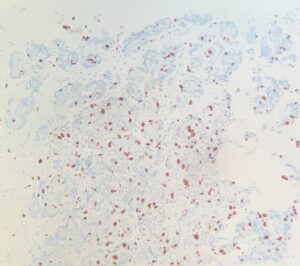

Ki-67

Por último, el Ki-67 es un marcador de proliferación celular. Un alto nivel de Ki-67 sugiere un crecimiento rápido del tumor, lo que podría requerir un tratamiento más agresivo.

Ki67 positivo. Núcleos marcados con DAB (marrón).